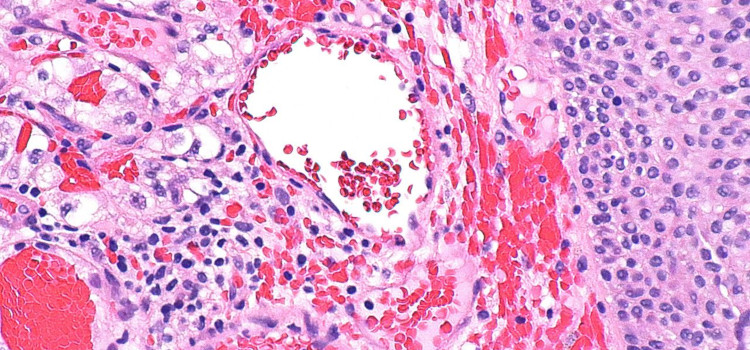

Equipo de Massagué en N.York abre vía para posible tratamiento de metástasis

Las células iniciadoras de metástasis emplean un truco para propagarse: cooptan las capacidades naturales de curación de heridas del cuerpo